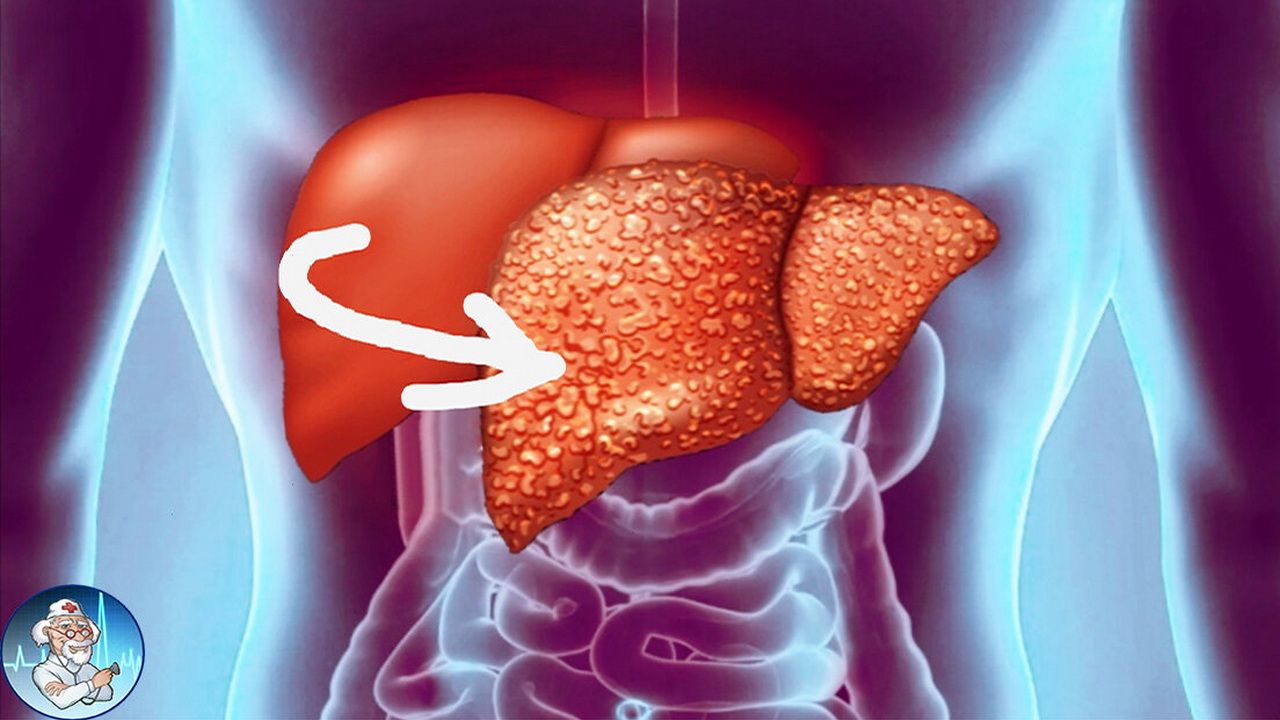

Изображения заболеваний печени: признаки и симптомы